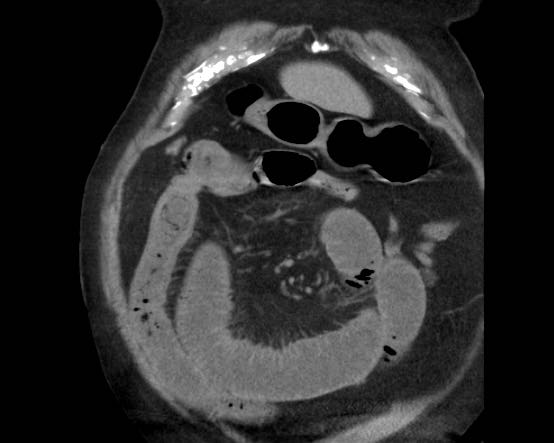

CT trong viêm túi mật cấp

CT có thể rất hữu ích trong các trường hợp siêu âm không cho kết quả chẩn đoán.

Đây là hình ảnh của một bệnh nhân béo phì với đau hạ sườn phải cấp tính trong 6 giờ. CRP 2.

Siêu âm cho thấy túi mật lớn có bùn mật, không quan sát thấy sỏi.

Việc ấn vào túi mật không đáng tin cậy do vị trí cao dưới cung sườn phải.

Không có bất thường siêu âm nào khác.

CT thực hiện cùng ngày cho thấy túi mật lớn với chỉ những thay đổi quanh túi mật kín đáo và không có nguyên nhân nào khác giải thích cho các triệu chứng.

Ngày hôm sau CRP là 105 và CT không tiêm thuốc cản quang lặp lại cho thấy quầng mờ xung quanh túi mật.

Phẫu thuật tiếp theo xác nhận viêm túi mật cấp giai đoạn sớm do sỏi nhỏ trong ống túi mật.